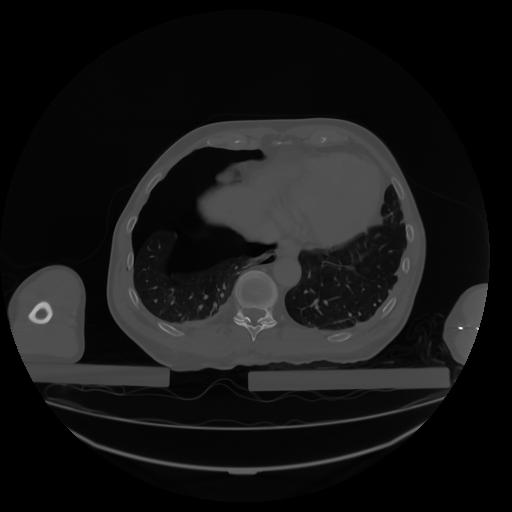

27 CUERPO,CE,Axial,3.0,CUERPO,,